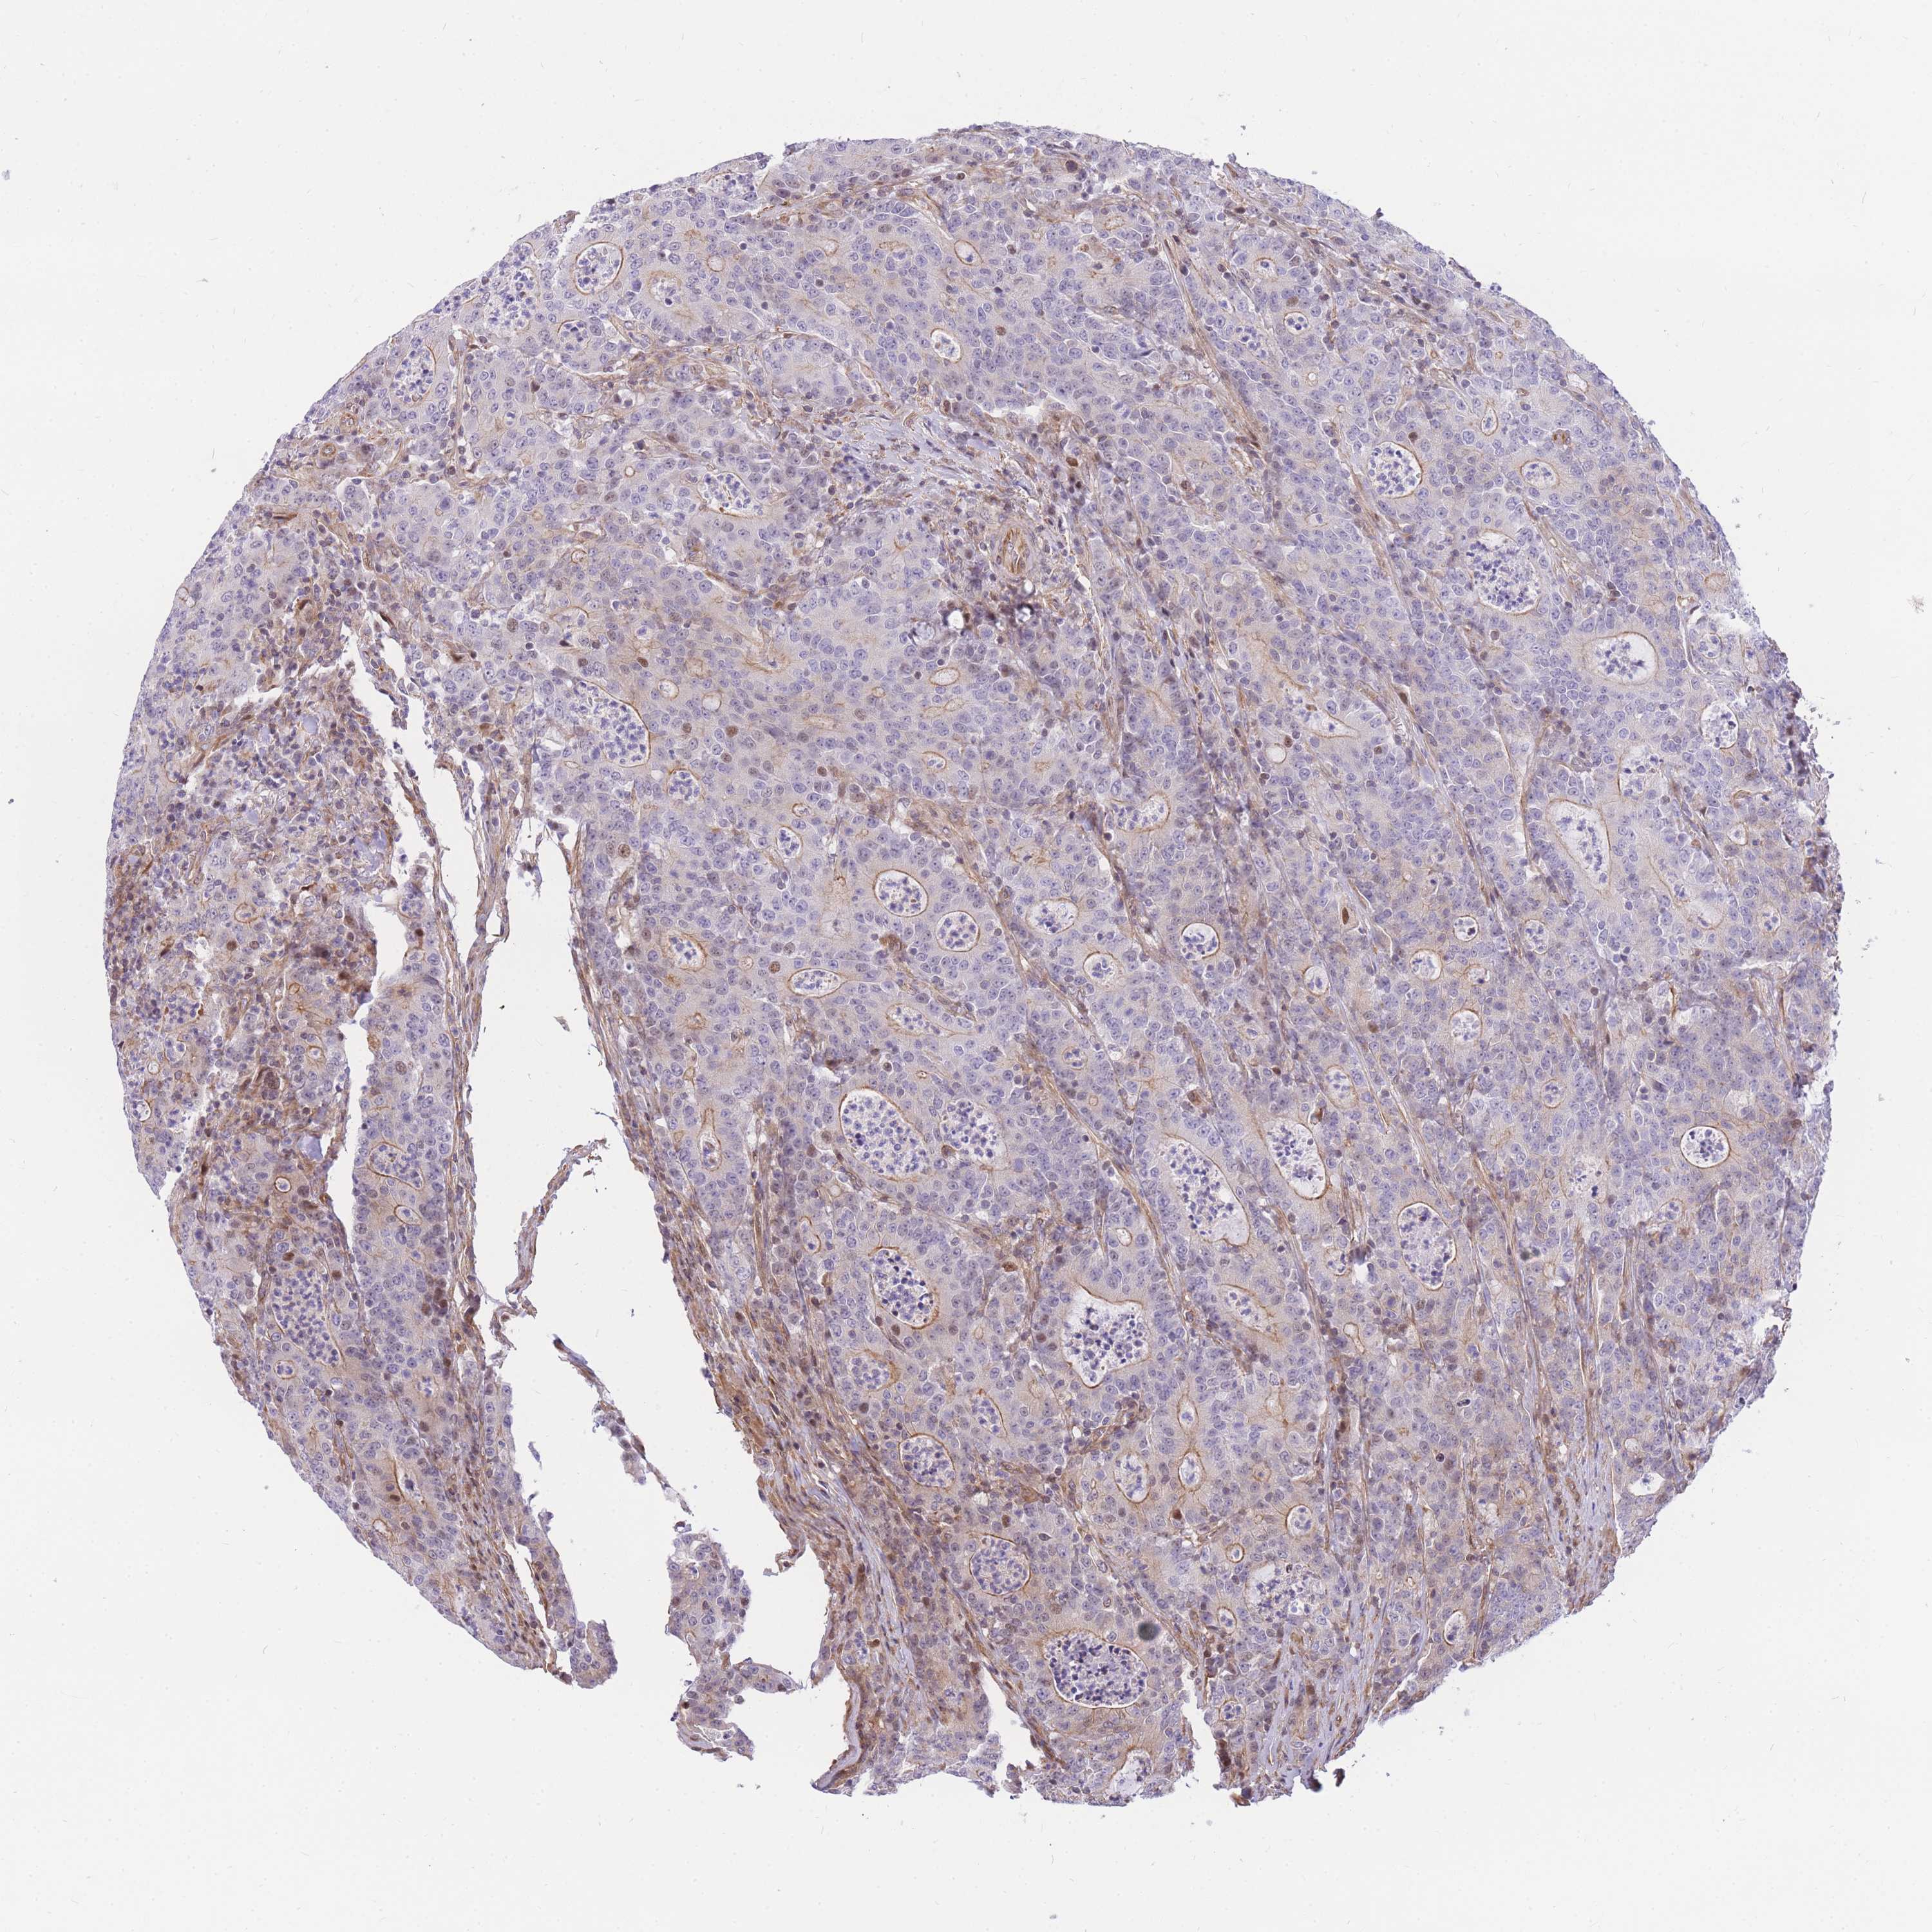

CANCER COLORECTAL CANCER Show tissue menu

Colorectal cancer

Colon adenocarcinoma